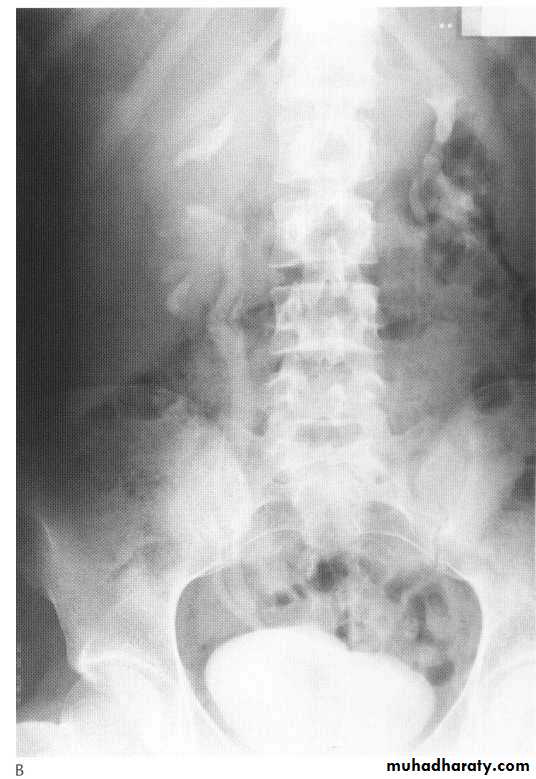

Polycystic kidneys

I n autosomal recessive polycystic disease of the kidneys (ARPCK) the renal parenchyma is replaced by numerous tiny (1-8 mm) cystsOn IVU there is a striated nephrogram thought to be due to contrast lying in the minority of preserved functioning tubules next to dilated non-opacified diseased tubules.